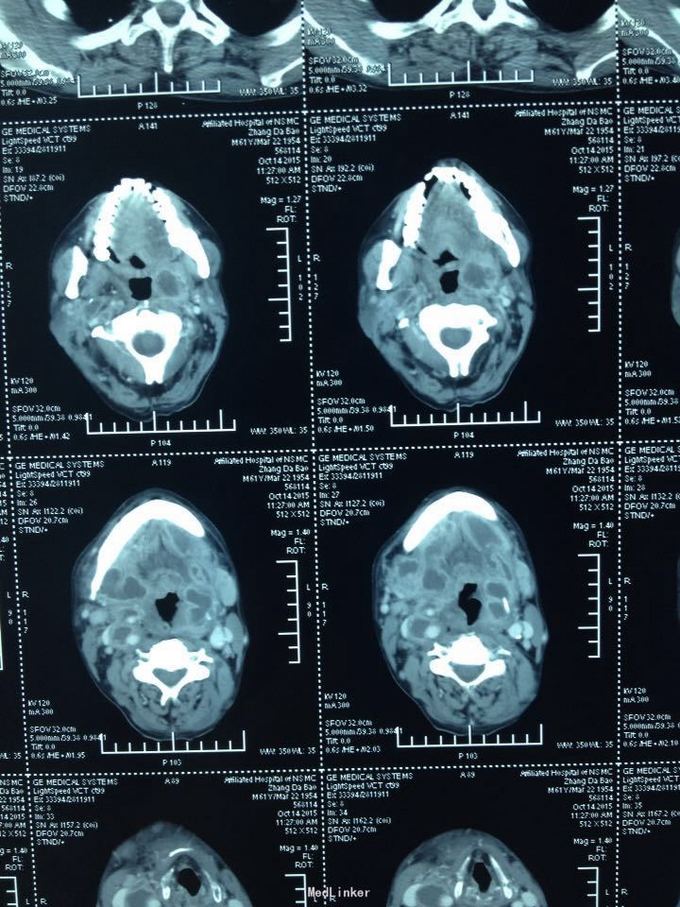

颈部肿痛10多天。10多天前无明显诱因出现颈部及颌下疼痛,肿胀明显,吞咽受限,无伴明显呼吸困难。无高热、寒战等。未特殊处理,上述症状渐加重。

双侧颈部肿胀明显,皮肤稍充血,皮温较高,可触及波动感,压痛明显,右侧为甚,咽部黏膜充血肿胀明显。

颈部多发脓肿。入院后完善相关检查,给予抗感染、对症支持治疗,并于急诊全麻下行颈部脓肿切开引流术,术中分离右侧颈动脉鞘,充分分离脓腔,充分引流。